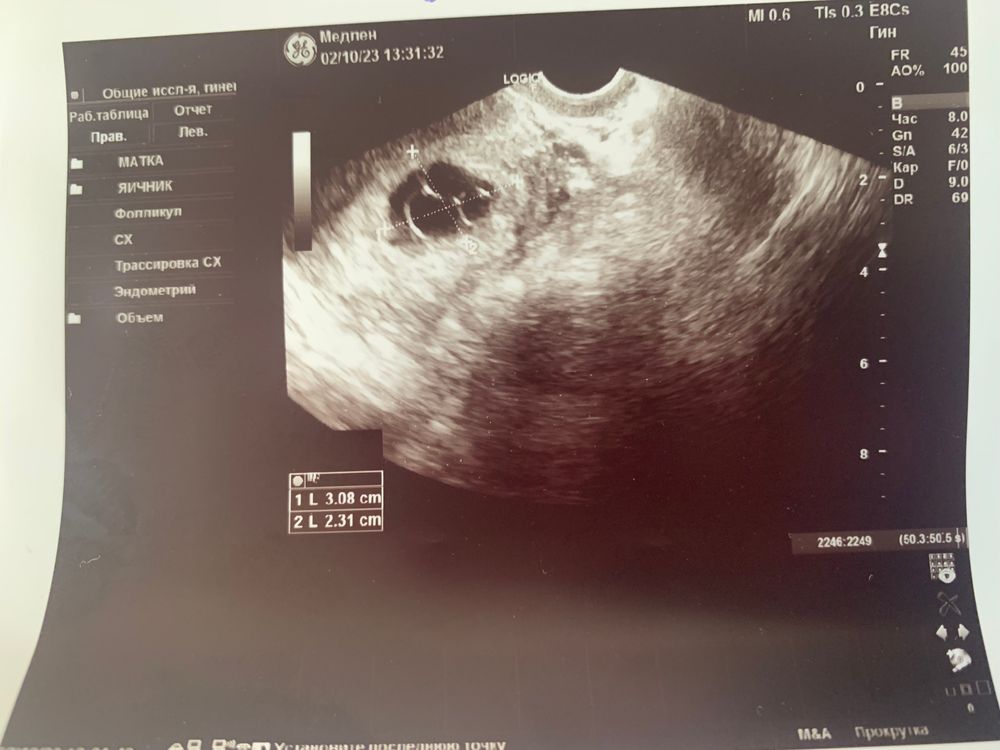

Сегодня на УЗИ сказали замершая, тройня. В надежде перерыла весь интернет с фото , думала вдруг все таки ошиблась врач (( но нет( 11 акушерских недель.

А до этого УЗИ не делали? Фото как на сроке 5 недель похоже. . Врач об эбрионах что-то говорила? Кажется их не видно.Сочувствую

Оля, делала, был маленький срок, потом уехала, не было возможности сделать УЗИ. Как вернулась в первый же день поехала. На сроке 5 недель (от зачатия) сказала ждать. Говорила видно но плохо. Отказывается уже тогда скорее всего было поздно.